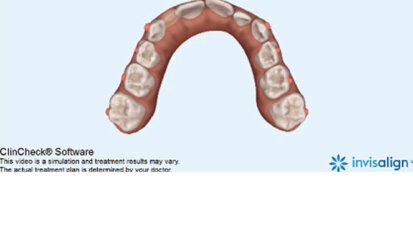

Bělení zubů a ortodoncie

St. 9. září 2020